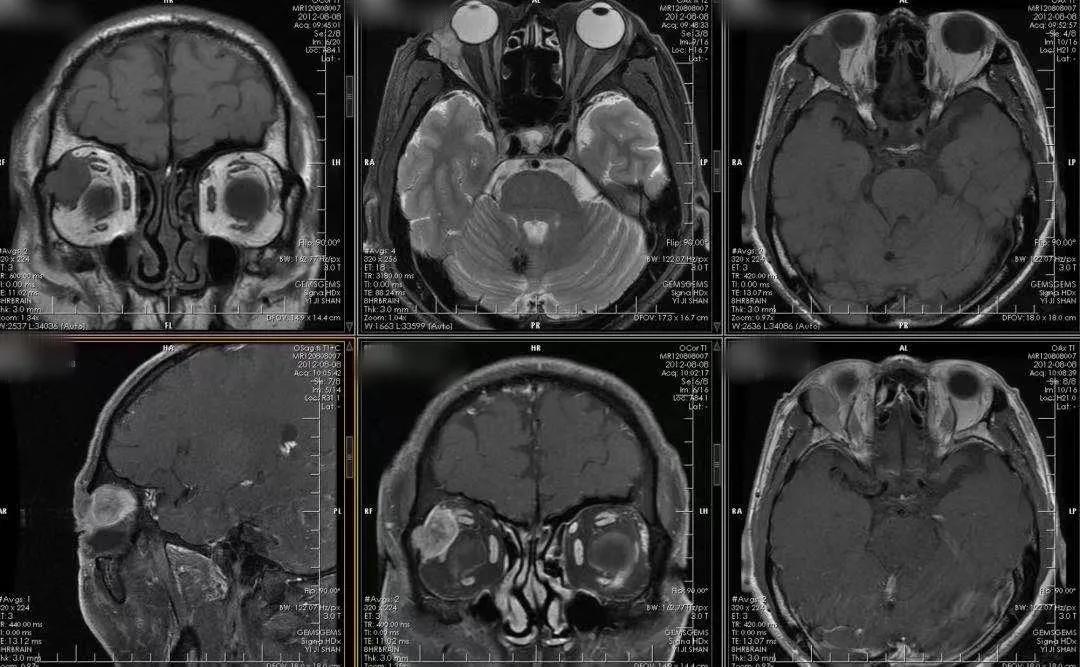

Ax: T1WI、fsT2WI、T1WI+C

Sag: fsT2WI、fsT1WI+C

Cor: T1WI、T1WI+C

眼眶MRI平扫+增强

右侧眼眶肌锥外间隙(泪腺区)类圆形混杂信号结节,局部与眼环、外直肌分界不清,眼球受压,增强后不均匀明显强化

故定性:恶性上皮性肿瘤